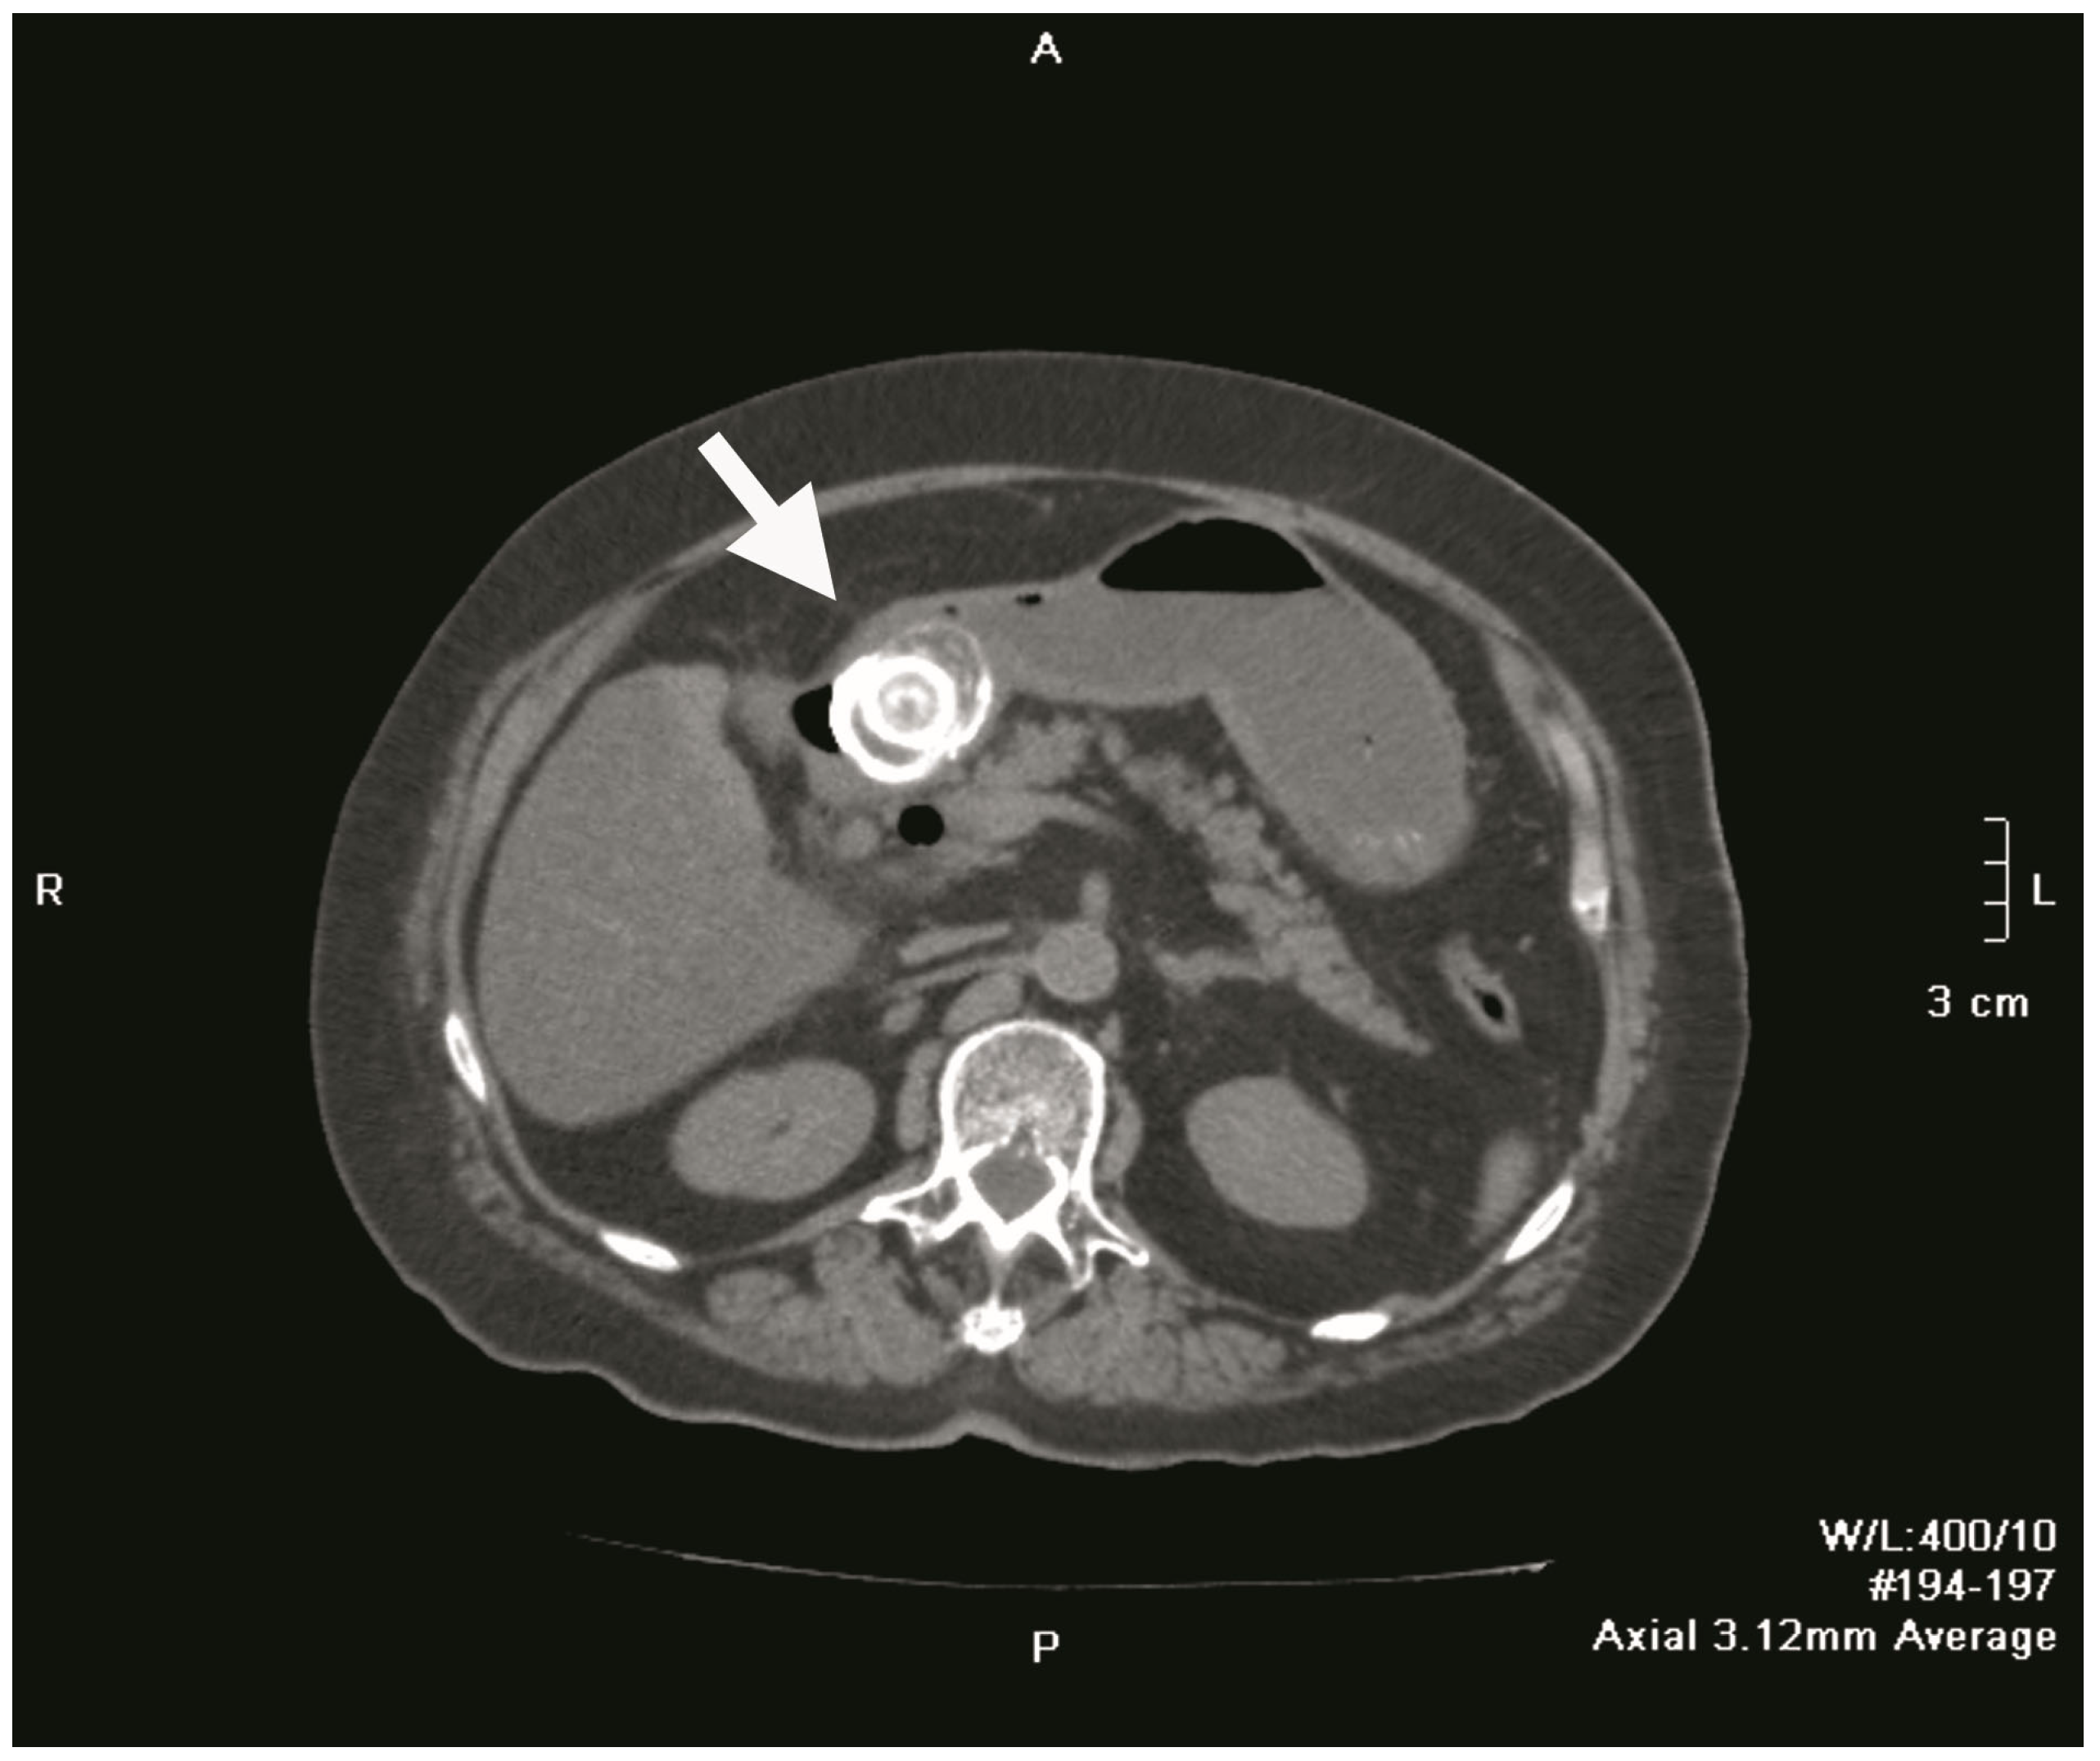

Plain abdominal radiography revealed a distended, fluid-filled stomach with signs of pneumoperitoneum (a result of gallbladder perforation; however, there was no secondary peritonitis because the process was blocked by the greater omentum) and obstruction. A 4 cm shadow of calcium intensity was noted in the right lumbar region. Abdominal ultrasonography demonstrated a partially distended, thick-walled gallbladder with multiple calculi, a finding consistent with chronic cholecystitis. Follow-up contrast-enhanced abdominal CT confirmed the presence of a cholecysto-duodenal fistula in the first part of the duodenum, with a 3.9 cm × 4.0 cm × 4.0 cm gallstone lodged in the proximal duodenum (Figure 1 and Figure 2). The scan also revealed sludge and calculi in the gallbladder, along with a distended, fluid-filled stomach and aerobilia.

Figure 1.

Axial non-contrast CT image of the upper abdomen revealing a large gallstone (white arrow) lodged in the duodenal bulb, a finding characteristic of Bouveret’s syndrome; the gallstone is obstructing gastric outflow and causing marked gastric distention. An air-fluid level is observed within the distended stomach.